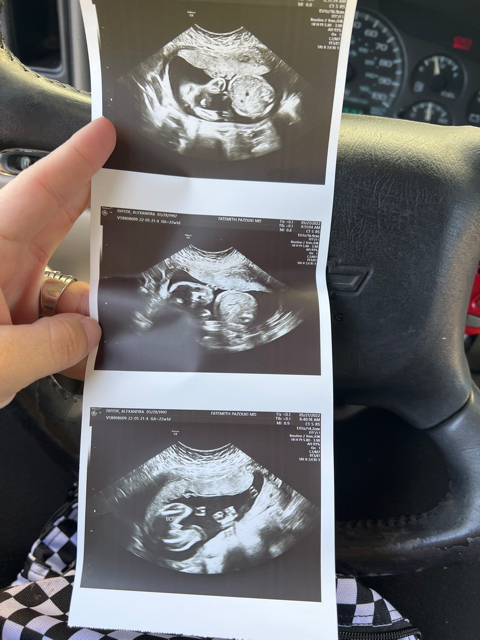

Head down question at 22 weeks

So I just had my anomaly scan, and everything was good, she said right as we finished up he’s head down by the way, and explained where he was on my belly and all that. Just wondering if that’s common at this point or do they typically move around still?